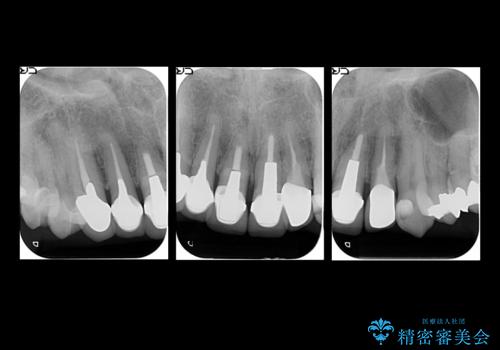

- 他の部位の治療で来院されていましたが、30年以上前に行った前歯のかぶせ物のきわがあっておらず虫歯になってきていました。

神経の治療から念のためやり直ししてからセラミックでかぶせました。

金属の土台が入っていましたがすべて外し、ファイバーコアでやり替えています。